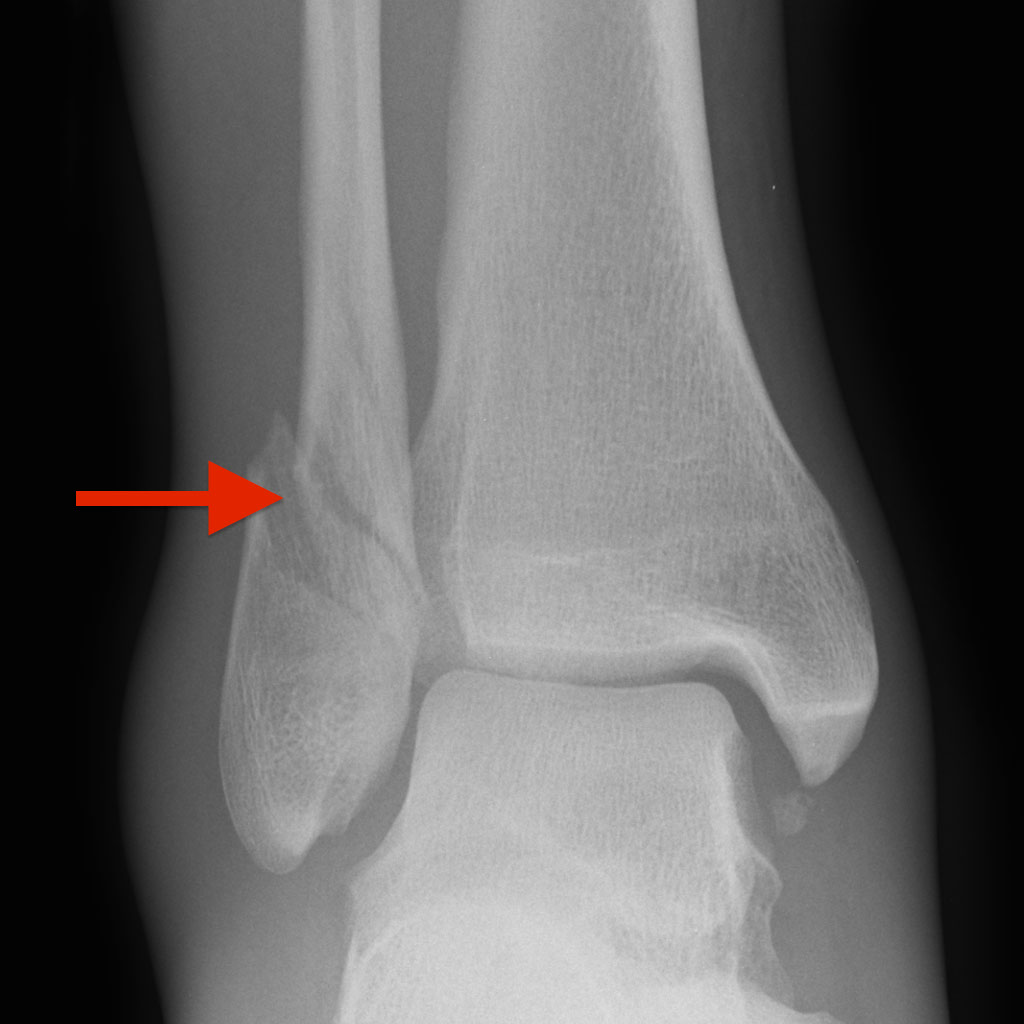

When a significant enough twisting force is placed on the foot, the ankle will bend. If this force is stronger than the binding strength of the ligaments, they will tear. This is the essence of an ankle sprain. As this force increases, the bones will also crack under the pressure. Ankle fractures have several different mechanisms depending on how the foot rotates on the ankle during the injury. The tibia and fibula can fracture independently or at the same time, and can be a simple chip all the way up to a spiral fracture that moves the bone out of place. The tibia can even fracture in two different places.

The problem lies when the bone moves out of position. The ankle has to function perfectly in place, and any displacement leads to ankle instability and eventual arthritis. The key to repairing these fractures is to ensure that the ankle is in as close to a normal position as possible, and hold it there while the bone mends. Sometimes only a cast or walking boot is necessary to hold the bone in place if the fracture is minimal enough. However, many cases require surgery to obtain the best result. The goal of surgery is to bring the ankle bones back to a normal position, and then use hardware (usually a combination of metal plates and screws) to keep the bone stable. As the ankle is protected exteriorly by a cast, the bone will mend and ideally the ankle will stay in a normal position, lessening the likelihood of arthritis developing. This recovery can take place over the course of six weeks to three months.